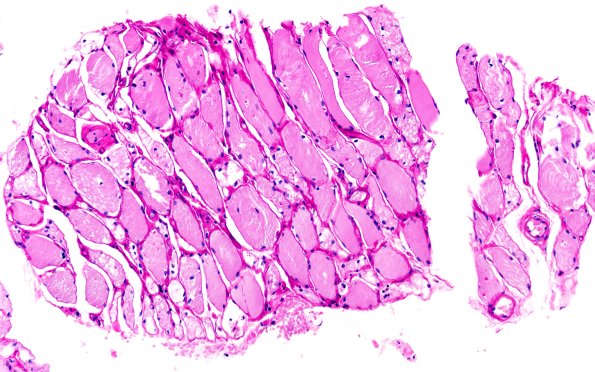

Washington University Experience | METABOLIC | Pompe Disease | 5B2 Muscle (Case 5) PAS with diastase 20X

PAS with diastase digestion was performed to evaluate glycogen stores. The muscle shows strong cytoplasmic PAS labeling which was significantly diminished by diastase, consistent with glycogen deposition. However, as is typical for tissue processed for paraffin embedding, much of the glycogen appears to have been washed out. (PAS/PAS-D)